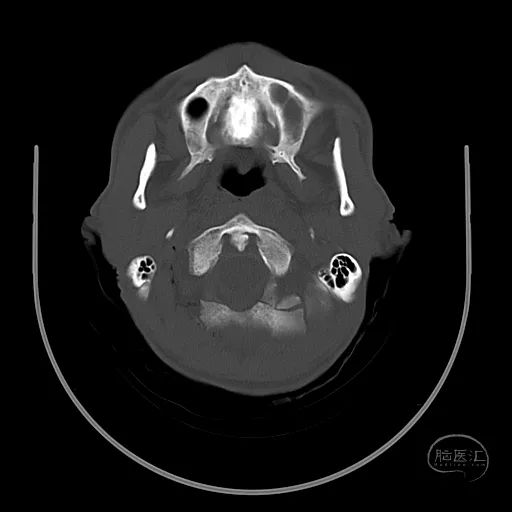

骨窗显示枕骨粉碎性骨折,累及枕骨大孔左侧,齿突尚居中。